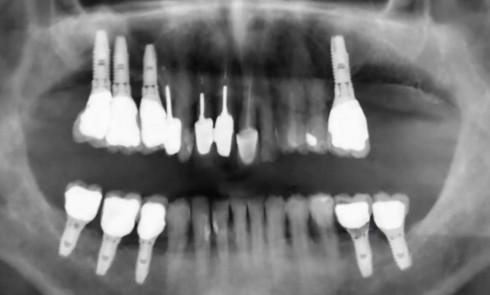

Article réservé à nos abonnés Extraction, implantation et temporisation immédiate : recycler la dent naturelle ? À propos d’un cas clinique

Les protocoles d’extraction-implantation immédiate, décrits pour la première fois en 1976 par Schulte et Heimke [1], se sont progressivement développés...